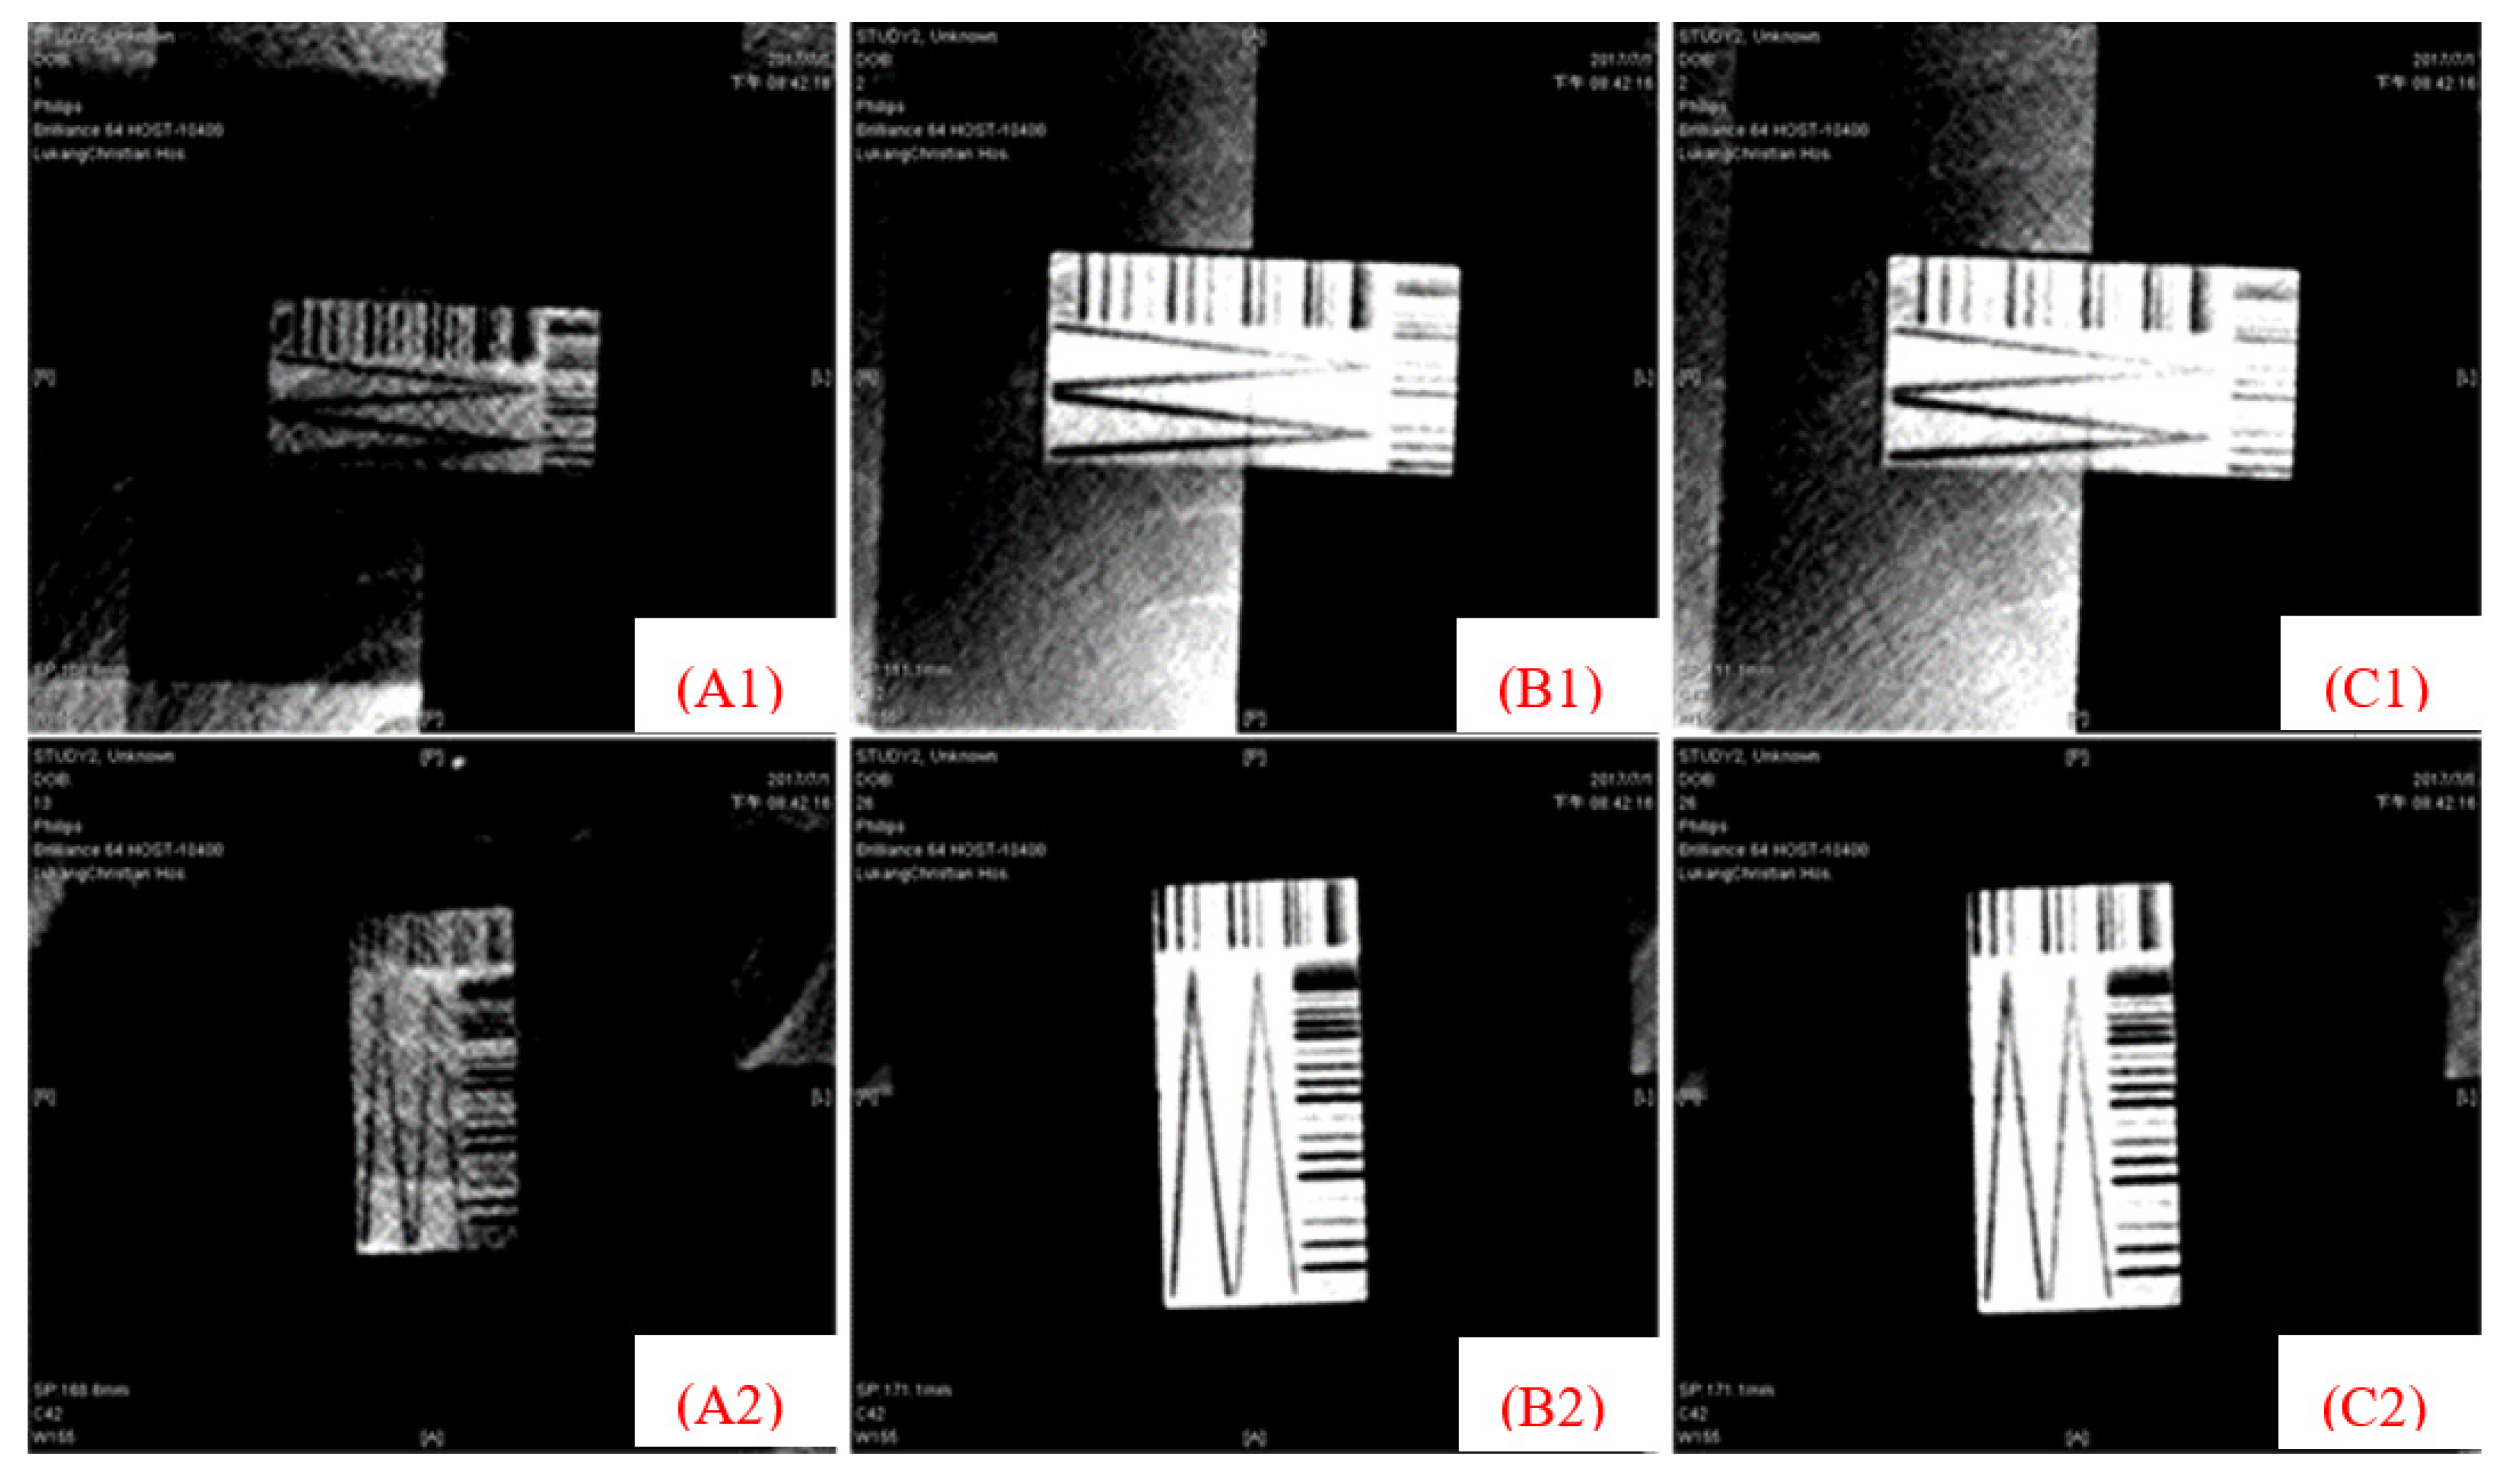

2.2. Slit Gauge

2.6. Grading the Gauge and Verification